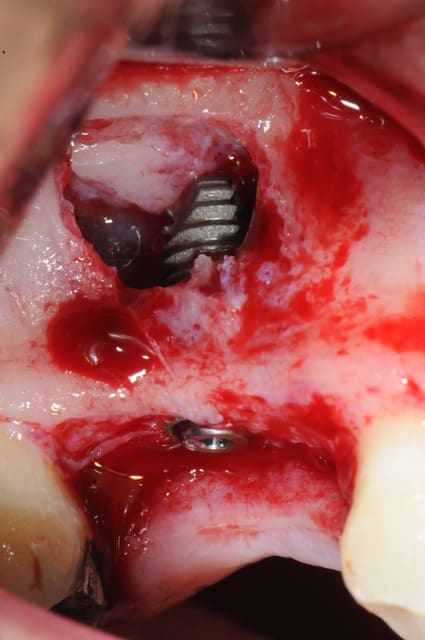

- mise en place de l'implant

- séchage discret de la surface osseuse

- injection du Vital Os en palatin et partout autour de l'implant

- hé hé hé ... pas de membrane de recouvrement, le matériaux se suffit à lui même. d'où une petite économie substantielle pour ceux qui ont l'habitude de mettre systématiquement une membrane après un Caldwell-Luc.

- sutures...